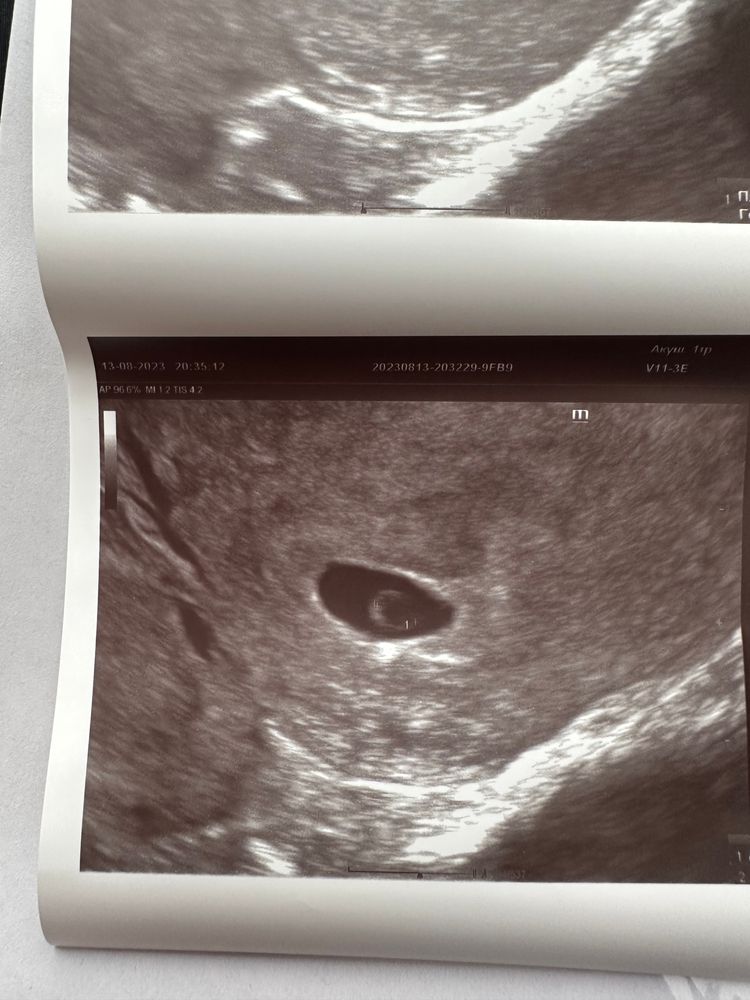

Сходила на узи и тревожусь

Темная Лошадка, меня смущает мое маленькое плодное яйцо 🙈

Поздравляю, у вас даже эмбриончик заподозрили! 🙌 все отлично же, жм отличный. Дайте себе отдохнуть от стресса, он вам точно не показан в беременность. Постарайтесь не накручивать себя, новости же отличные